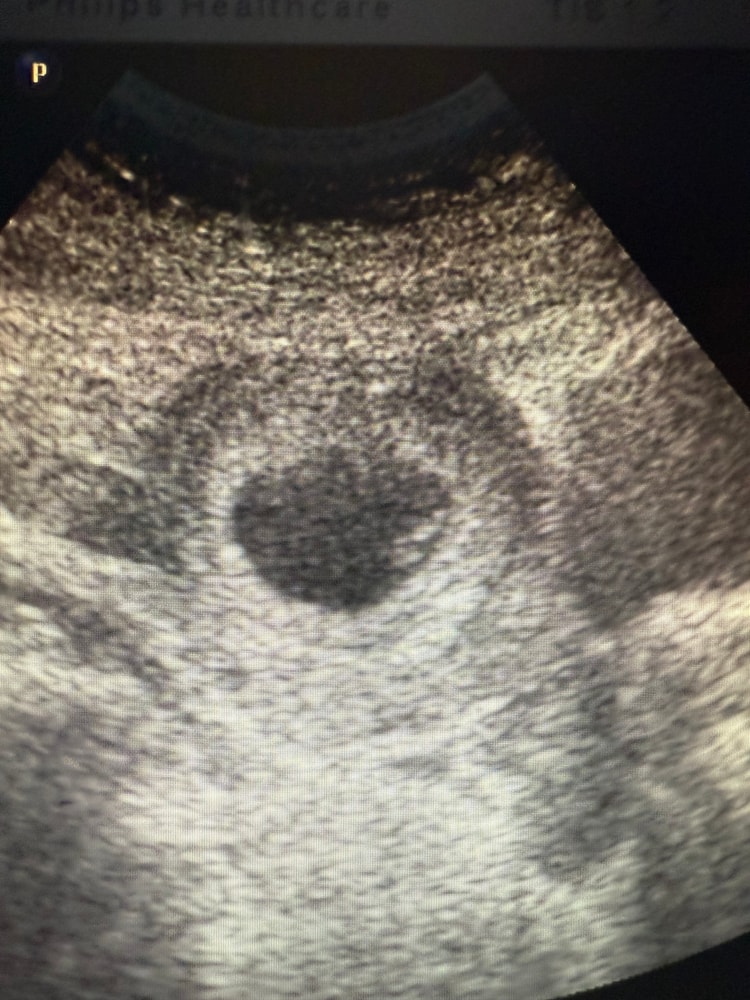

УЗИ в 8 недель

УЗИ, КТГ, доплерКороче сходила сегодня на УЗИ. Посмотреть на гематому и уже нормально глянуть эмбриона и сб ибо на узи в 6 с копейками меня напугали отсутствием эмбриона, разницей в сроках в 2 недели и РХГ. И ура, гематомы нет, эмбрион есть, сб+ сроки в норме соответствуют 7-8 неделям. Фото на память как самое-самое первое😁